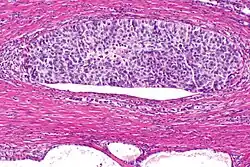

Gruczolakorak prostaty (obraz mikroskopowy, barwienie hematoksyliną i eozyną)

Gruczolakorak gruczołu krokowego, obraz mikroskopowy

W prawej górnej części preparatu obecny gruczolakorak, obok widoczne są prawidłowe gruczoły tworzące utkanie stercza

Większość guzów powstaje w strefie obwodowej gruczołu krokowego[151][152]. W 85% przypadków nowotwór jest wieloogniskowy[153]. Makroskopowo guzy są trudne do odróżnienia od otaczającej tkanki, twarde, lite, na przekroju barwy od białoszarej do żółtej[154][152]. Guzy mogą deformować obrys narządu. Typowo guzy widoczne makroskopowo mają tendencję do wyższego stopnia zaawansowania i złośliwości w porównaniu do zmian niewidocznych makroskopowo, które często klinicznie nie były badalne palpacyjne. W obrazie makroskopowym rzadko są obecne obszary krwotoczne lub martwicy[154]. Typowo nowotwór szerzy się poza granicę zasięgu makroskopowego[154].

W obrazie mikroskopowym gruczolakoraki gruczołu krokowego znacznie różnią się stopniem zróżnicowania (złośliwości histologicznej), dając spektrum nowotworów od dobrze zróżnicowanych (o niskiej złośliwości), które trudno odróżnić od prawidłowego utkania gruczołu krokowego do zmian o niskim zróżnicowaniu (o wysokiej złośliwości)[155]. Cechą wspólną dla wszystkich raków stercza jest obecność pojedynczej warstwy jednego typu komórek bez warstwy podstawnej, która jest widoczna w prawidłowych cewkach gruczołowych[156][152].

W dobrze zróżnicowanych nowotworach komórki nowotworowe tworzą stłoczone cewki gruczołowe o nieregularnym kształcie i różnej wielkości, które są wyścielone przez jedną warstwę komórek. Cewki gruczołowe są ułożone w dość bezładny sposób[156]. Kolejnym wzorem utkania typowym dla nacieku jest obecność atypowych struktur gruczołowych między dużymi, prawidłowymi gruczołami. Wraz z utratą różnicowania i tworzeniem struktur sitowatych, połączonych gruczołów lub słabo uformowanych gruczołów, coraz bardziej zaznacza się różnica między łagodnymi gruczołami a strukturami tworzonymi przez komórki nowotworowe[156]. Nisko zróżnicowane nowotwory są zbudowane z litych arkuszy lub sznurów komórek, a cewki gruczołowe są nieliczne lub poronne[156][157].

Komórki cechują się obecnością powiększonego jądra komórkowego i powiększonego jąderka. W niektórych komórkach nie jest obecne powiększone jąderko, jednak pozostają powiększone i hiperchromatyczne[158][159]. Figury mitotyczne mogą być liczne w nowotworach o wysokiej złośliwości[158]. Cytoplazma komórek budujących struktury gruczołowe jest amfifilna, w jej obrębie nie stwierdza się lipofuscyny[158].

Może być widoczna inwazja naczyń krwionośnych i chłonnych oraz nerwów, która jednoznacznie przemawia za złośliwym charakterem nowotworu[159]. Innymi cechami wskazującym na złośliwość nowotworu jest obecność struktur przypominających kłębuszki oraz niewielkich guzków zbudowanych z eozynofilnych włókien w obrębie cewek gruczołowych (mucinous fibroplasia, collagenous micronodules)[160][159]. W cewkach gruczołowych bywa obecna mucyna, ale jej obecność nie jest swoista dla raka. W guzach o niskiej złośliwości są obecne krystaloidy (prostatic crystalloids) widoczne jako ostre, gęste eozynofilne struktury o różnych kształtach geometrycznych obecne w świetle cewek, jednak ich obecność nie jest charakterystyczna dla raka[158][159].